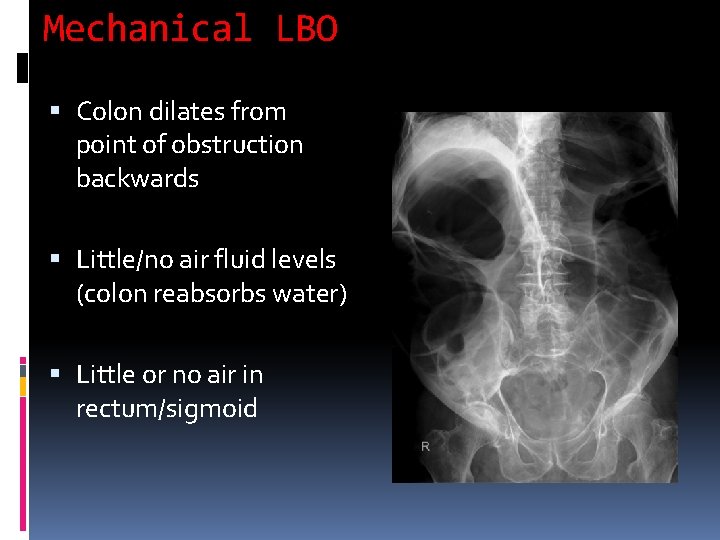

Mechanical LBO Colon dilates from point of obstruction backwards Little/no air fluid levels (colon reabsorbs water) Little or no air in rectum/sigmoid